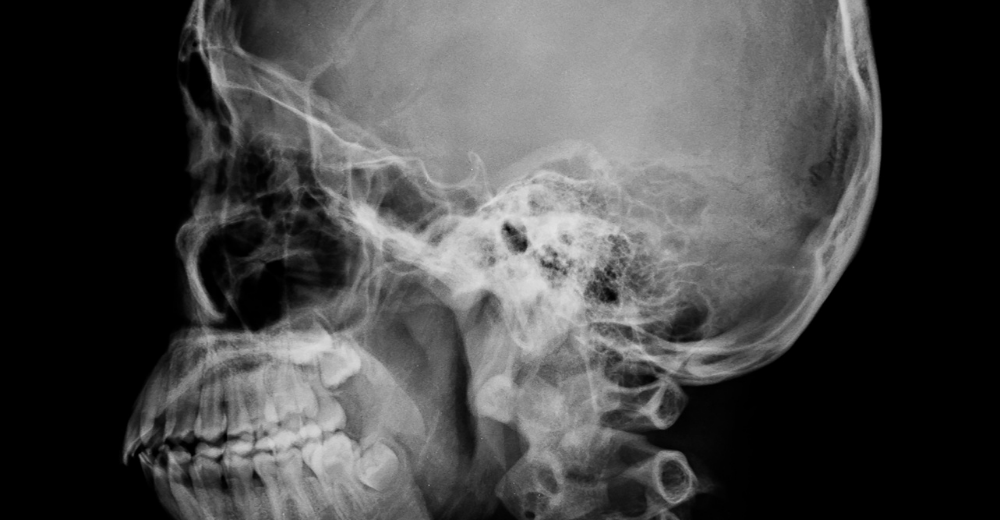

La RX Sella Turgica, o radiografia della sella turcica, è un esame diagnostico che permette di ottenere immagini dettagliate della sella turcica, una piccola depressione ossea situata alla base del cranio. Al suo interno si trova l’ipofisi, una ghiandola endocrina essenziale per la regolazione di numerosi processi fisiologici, come il metabolismo, la crescita e la funzione riproduttiva.

L’esame viene svolto in modo semplice e non invasivo presso il Poliambulatorio S-Medical Group di Sora. Il paziente viene fatto accomodare sul lettino radiografico e posizionato in maniera tale da consentire la visualizzazione ottimale della sella turcica. Attraverso l’utilizzo di raggi X, vengono catturate immagini da diverse angolazioni per garantire una valutazione completa della struttura ossea e dei tessuti circostanti. L’intero procedimento dura generalmente tra i 15 e i 30 minuti e non richiede anestesia.

La RX Sella Turgica consente di identificare numerose condizioni patologiche che interessano la sella turcica e l’ipofisi. Le immagini ottenute possono rivelare: